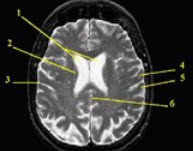

分别标出如图所示1_______________2_______________3_____________4___________5____________6_______________部位。